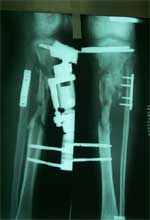

术前X线片,骨折后2年骨缺损、骨不连     术后6个月X线片,新骨桥接骨缺损